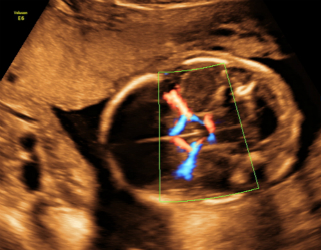

4.分娩前超声检查:超声重点观察指标包括:胎方位、胎儿大小、胎盘及胎儿循环、羊水量、胎盘成熟度、有无胎盘早剥或前置胎盘、脐带有无绕颈、脱垂等。这些指标对临产时医师选择正确的分娩方式,对母亲及胎儿健康平安至关重要。尤其对在整个孕期从未接受超声检查的准妈妈,为了母子的平安,分娩前务必接受一次超声检查。